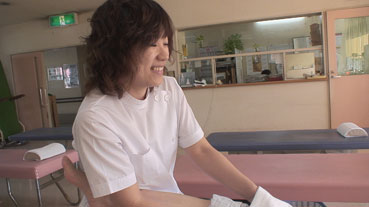

リハビリを毎日行っている。

傷口は治って、傷跡は残っているが、順調のようだ。 |

11月15日、リハビリの様子を見た。 |

あと、中川先生による足のマッサージだ。 |

| 毎日、このような足の風呂、中川先生によるマッサージなどリハビリを行う。 |

| これらの治療を受け、バンジャの足はだんだん治ってくる。 |